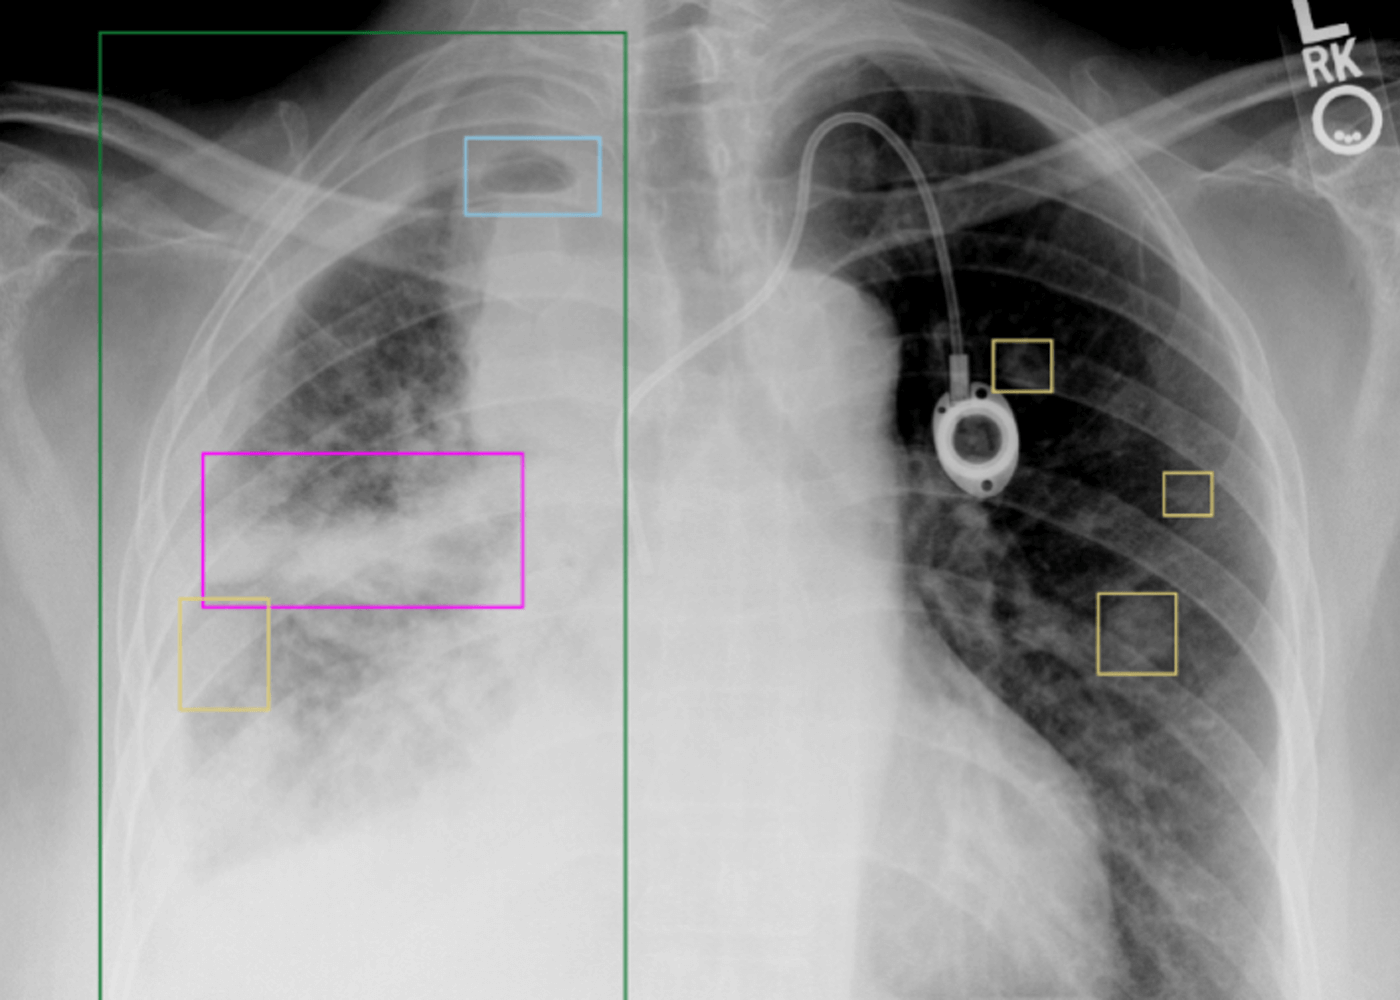

Chest X-ray pathologies box-labeling